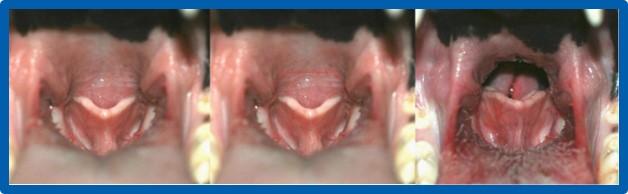

• Voile du palais trop long et épais

• Saccules laryngés éversés

• Raccourcissement du voile du palais (staphylectomie ou palatoplastie)

• Résection des saccules laryngés (sacculectomie)

• L’ablation des amygdales (amygdalectomie)